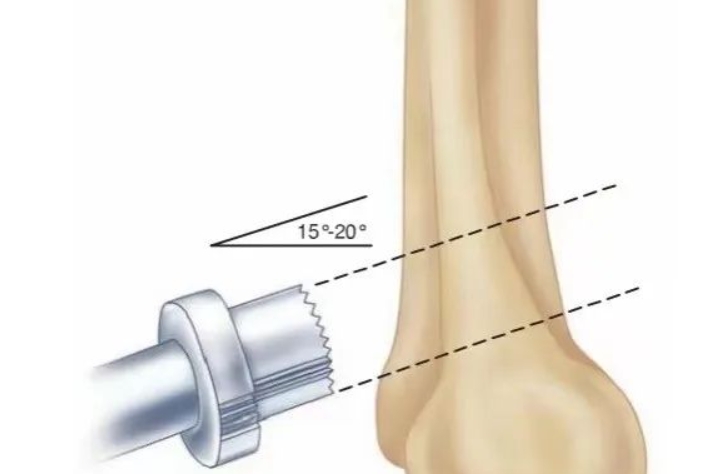

胫骨后叉止点骨折可分为三型,I型为无移位骨折,通常可保守治疗,对II型和III型移位骨折,通常采取手术治疗,以恢复膝关节稳定性。 关节镜下Endobutton固定后叉止点骨折因其微创、固定有效等优点,已成为治疗的首选。但关节镜手术技术要求高,因此,有学者采用自制钩钢板切开复位固定后叉止点骨折,取得了良好效果。结果发表在2021.07 Injury期刊上。